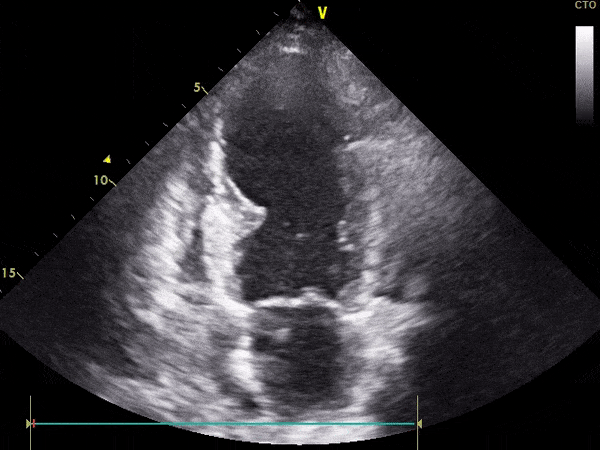

TTE

Ekokardiografi transtorakale triplex (2D, color, doppler) ose e njohur ndryshe si eko e zemrës, është e domosdoshme për të parë funksionimin e zemrës dhe lëvizshmërinë e mureve të saj.

Pamje të kapura me TTE: